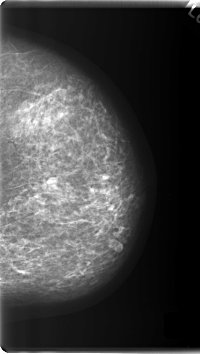

C_0213_1.RIGHT_CC

LEFT_CC LINES 6016 PIXELS_PER_LINE 3384 BITS_PER_PIXEL 12 RESOLUTION 50 NON_OVERLAY

RIGHT_CC LINES 6032 PIXELS_PER_LINE 3928 BITS_PER_PIXEL 12 RESOLUTION 50 OVERLAY